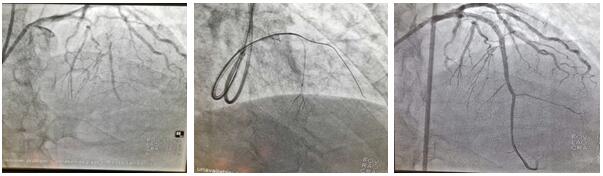

患者劉某某, 68歲男性,1月前于我院診斷:急性非ST段抬高型心肌梗死。行冠脈造影提示前降支近段100%閉塞,同側(cè)穿膈支側(cè)枝循環(huán)形成,回旋支近中段狹窄80%-90%,LAD為CTO病變,擬行完全血運重建治療,順利于回旋支病變處植入1枚支架,術(shù)中反復嘗試各種導絲均未能開通LAD血管,歷時近3小時,只能放棄,擇期再處理。面對困難,面對失敗,心血管二病區(qū)左梅主任醫(yī)師團隊,反復閱片,尋找失敗原因,知難而上,勇于挑戰(zhàn),制訂新的手術(shù)策略,決定為患者第二次開通LAD閉塞病變。在經(jīng)過充分的術(shù)前討論后于2020年7月2日第二次上臺,由于患者LAD近段CTO病變,前次正向途徑介入失敗,右冠無良好側(cè)枝形成,無逆向條件,擬行乒乓技術(shù)同側(cè)微導管造影顯示閉塞遠段,提供正向?qū)Ыz的指引,進入遠端血管真腔;若失敗,微導管跟進至血管內(nèi)膜下,采用ADR(正向內(nèi)膜下重回真腔)技術(shù)完成手術(shù)。手術(shù)的重要點在于控制血腫的大小。術(shù)中采用同側(cè)雙指引導管至左冠脈開口(乒乓技術(shù)),在一側(cè)指引導管送微導管至穿膈支中段,超選擇造影清晰顯示LAD-CTO遠段,另一側(cè)指引導管內(nèi)反復調(diào)試FieldXT-A導絲順利通過閉塞病變至遠段,在助手及導管室工作人員的全力配合下,歷時不到1小時,成功完成手術(shù)。術(shù)中患者無任何不適及并發(fā)癥發(fā)生,一家人很是欣喜。